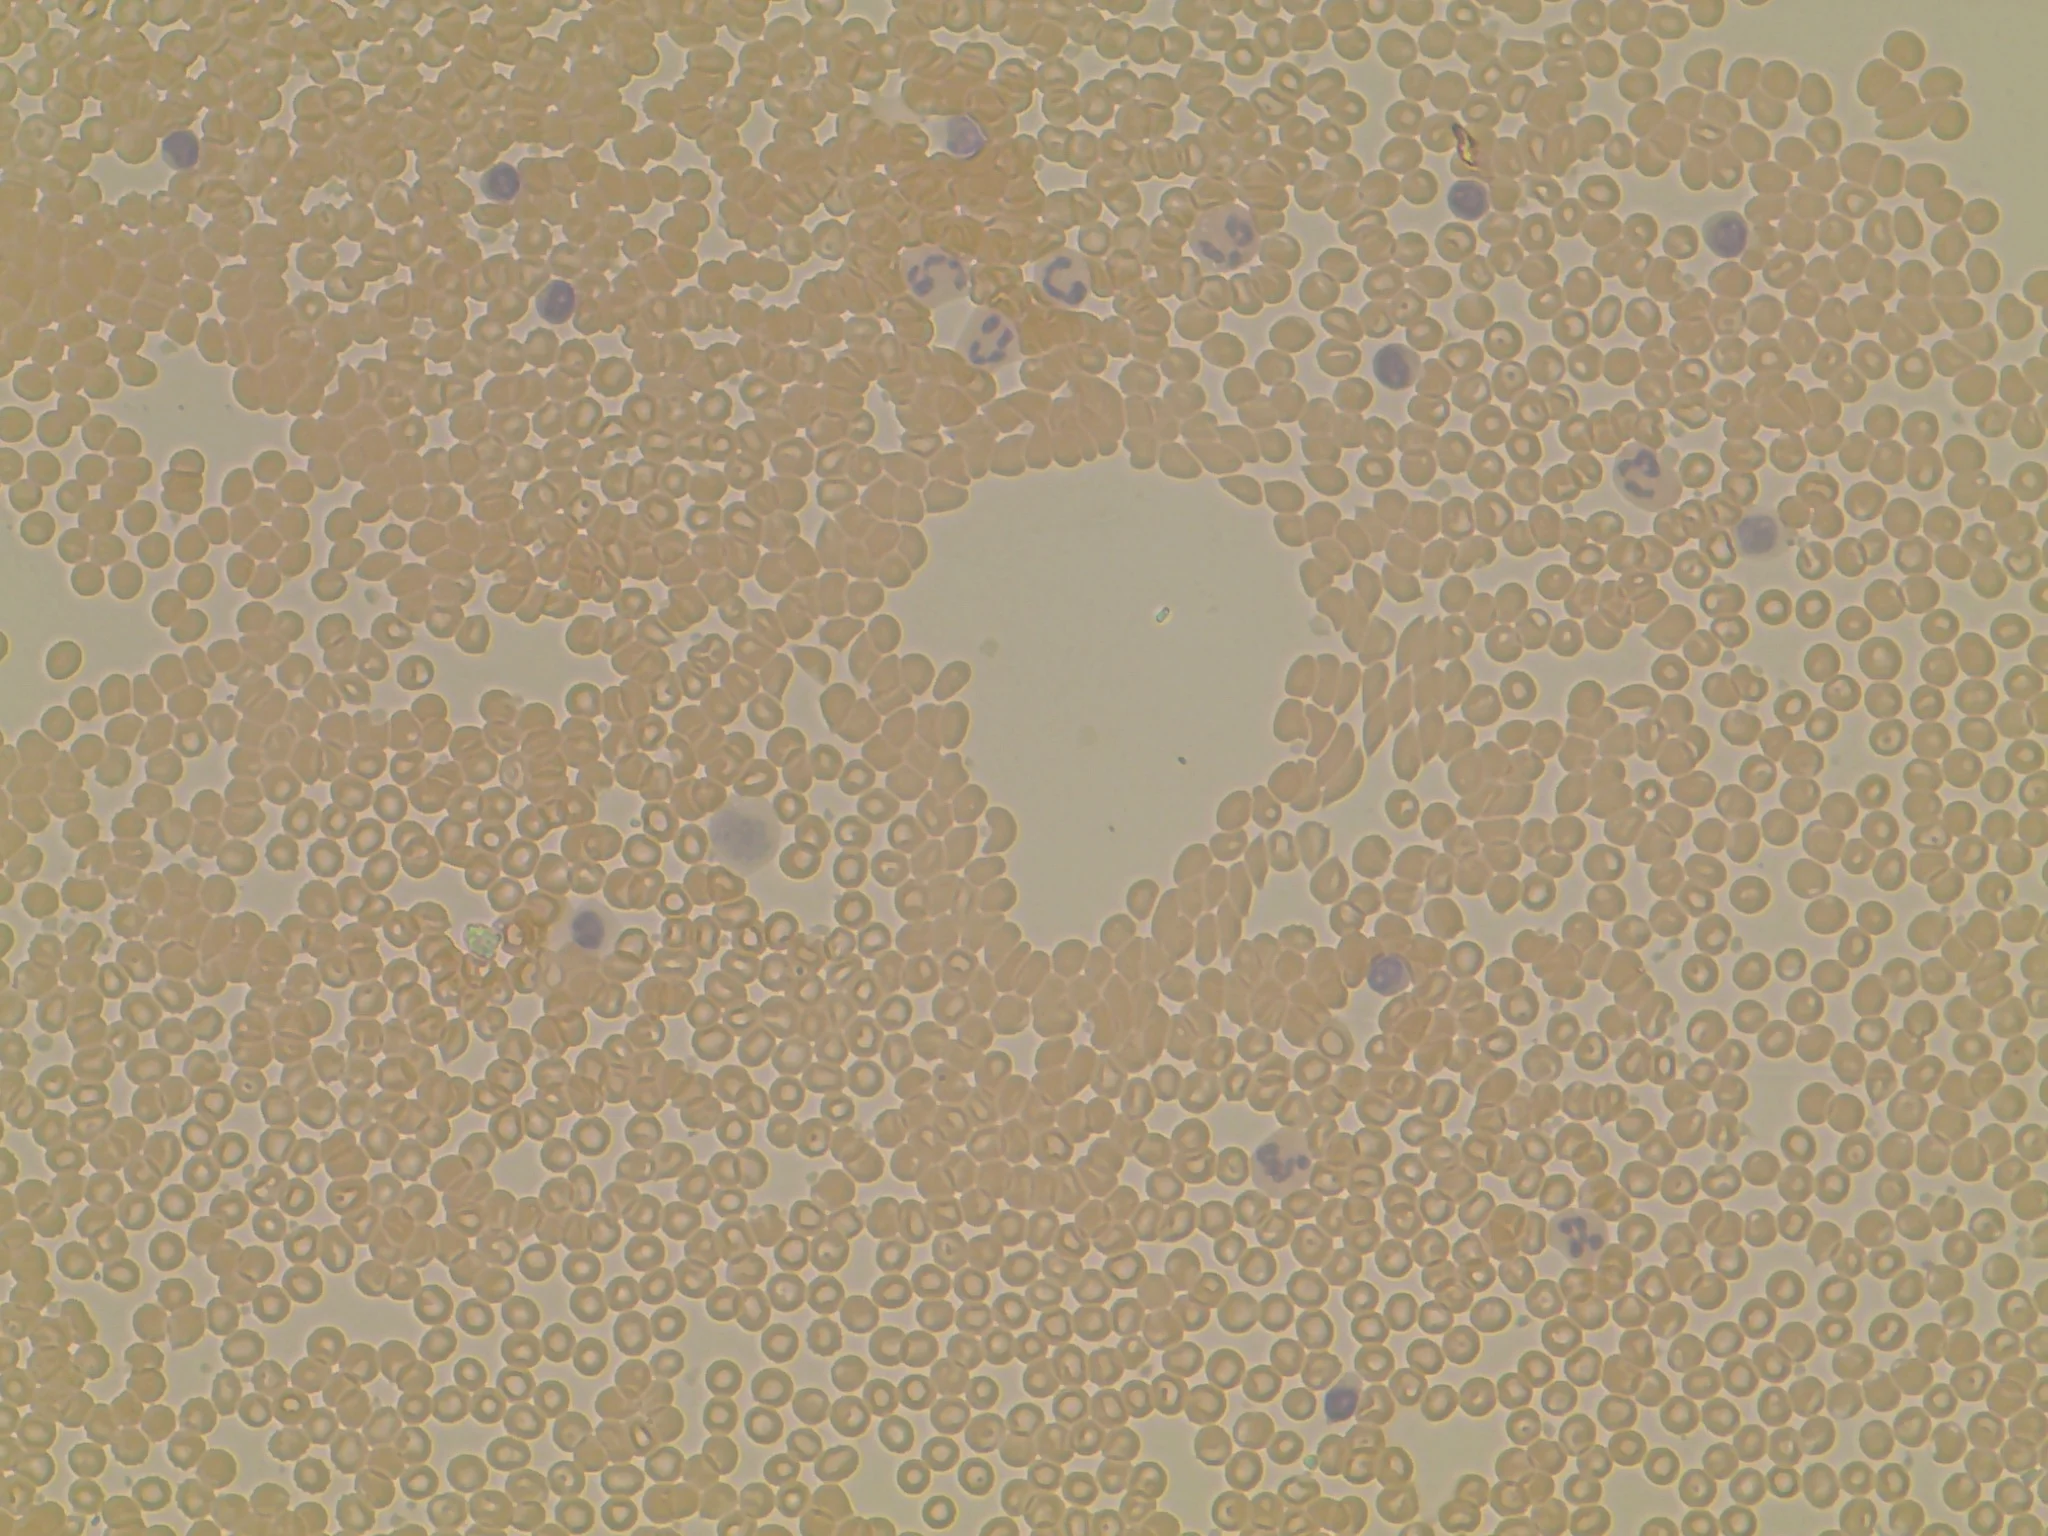

Monocytes differentiate into heterogeneous populations of tissue macrophages and DCs that regulate inflammation and immunity. Identifying specific populations of myeloid cells in vivo is problematic, however, because only a limited number of proteins have been used to assign cellular phenotype. Using mass spectrometry, we identified 106 plasma membrane protein markers of M-CSF-derived macrophages, classically and alternatively activated macrophages, and GM-CSF-derived DCs. In our own work, we used these markers to demonstrate that thioglycolate elicited peritoneal macrophages resemble GM-CSF-derived DCs, a result which we confirmed using genetic and functional approaches. In collaborative studies, we applied these surface markers to interrogate the phenotype of macrophages in atherosclerotic plaques, lymph nodes, and tumors.